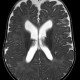

Dok ada kasus seorang anak usia 1 tahun. Riwayat lahir prematur. Pada usia 3 bulan dicurigai adanya hidrosefalus dari pemeriksaan fisik dan USG. Namun saat diperiksa dengan MRI, ada 2 dokter bedah saraf yang memiliki pendapat berbeda, 1 mengatakan benar ada namun minimal di extracranial dan 1 dokter lagi mengatakan bahwa TIDAK ADA hidrosefalus. Hal tersebut membuat bingung orangtua pasien. Pada usia 1 tahun ini, apa yang harus dilakukan oleh orangtua pasien tersebut dok, perlukah MRI ulang? Keadaan anak saat ini secara fisik tidak terlihat kelainan, perkembangannya masih sesuai usianya jika disetarakan dengan usia lahirnya.

Hidrosefalus adalah kondisi dimana produksi, distribusi, atau eliminasi cairan serebrospinal terganggu, sehingga menyebabkan akumulasi CSF dalam sistem ventrikel kepala.

Kasus yang dokter deskripsikan memiliki beberapa faktor, antara lain prematuritas, ukuran kepala yang membesar, dan tumbuh kembang yang normal.

Prematuritas meningkatkan kemungkinan terjadinya perdarahan intraventrikular pada bayi, yang dapat menimbulkan hidrosefalus. Makrosefali, yaitu ukuran kepala yang melebihi persentil 75, juga perlu dicurigai adanya hidrosefalus.

Perlu diingat bahwa pada beberapa anak, dapat terjadi Benign enlargement of the subarachnoid spaces (BESS) yaitu suatu variasi normal dengan ukuran kepala besar.

Tumbuh kembang yang normal merupakan tanda baik, karena hidrosefalus sering menyebabkan tumbuh kembang anak melambat.

2. Melakukan MRI kepala non kontras, dan membawa MRI yang lama sebagai pembanding. Bila memang kondisi hidrosefalus, maka akan bertambah berat seiring waktu, sehingga perbandingan antara MRI sebelum dan MRI baru sangat penting.